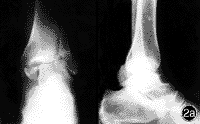

I度:單純內踝骨折,骨折緣由脛骨下關節面斜上內上,接近垂直方向。

II度:暴力較大,內踝發生撞擊骨折的同時,外踝發生撕脫骨折,稱雙踝骨折。

III度:暴力較大,在內外踝骨折同時距骨向後撞擊脛骨後緣,發生後踝骨折(三踝骨折)。

I度:單純內踝撕脫骨折,骨折線呈橫行或短斜行,骨折面呈冠狀,多不移位。

II度:暴力繼續作用,距骨體向外踝撞擊,發生外踝斜行骨折,即雙踝骨折。如果內踝骨折的同時脛腓下韌帶斷裂,可以發生脛腓骨下端分離,此時距骨向外移位,可在腓骨下端相當於聯合韌帶上方,形成扭轉外力,造成腓骨下1/3或中1/3骨折,稱為Dupuytren骨折。

III度:暴力過大,距骨撞擊脛骨下關節面後緣,發生後踝骨折,即三踝骨折。